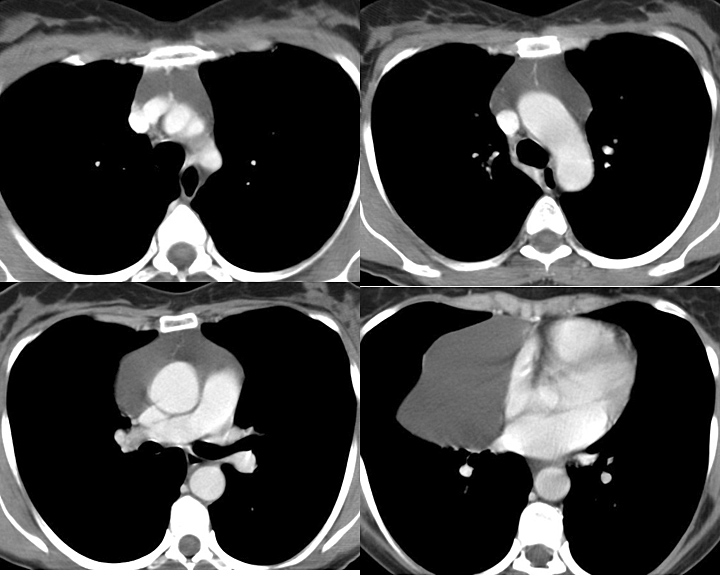

Fat Pad

Case 3c